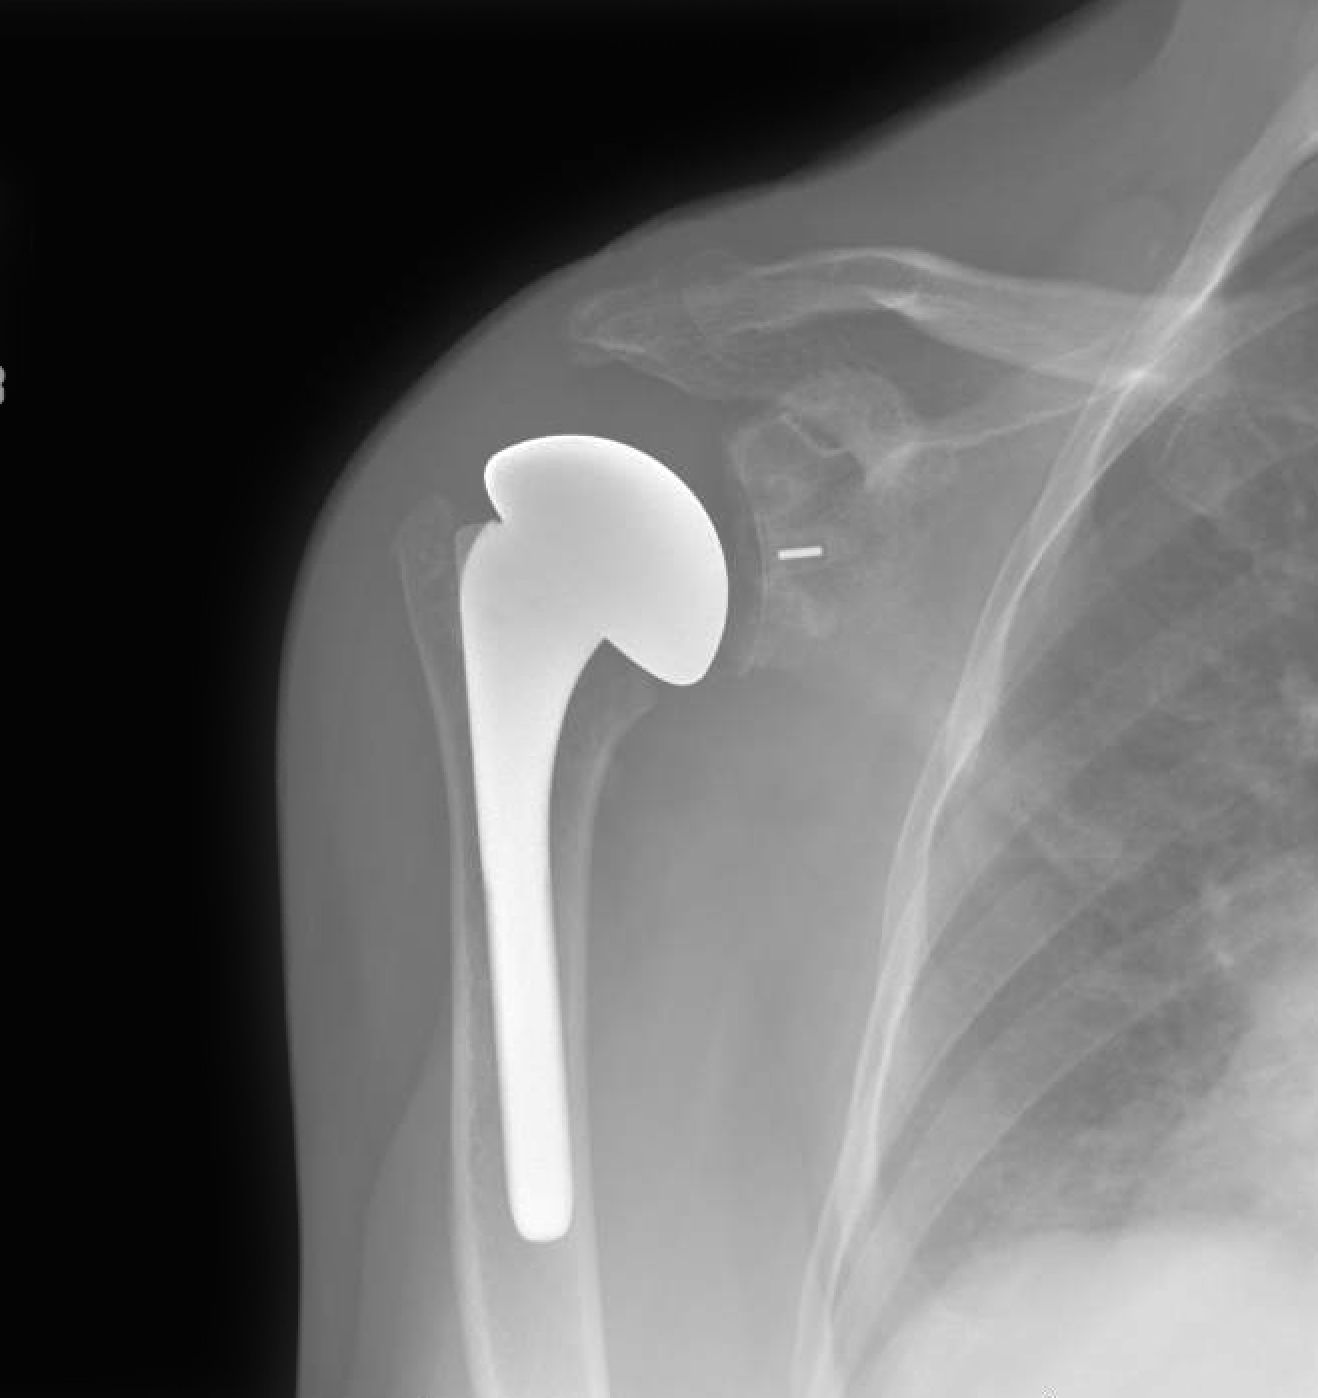

What Happens If Shoulder Replacement Fails . If the artificial shoulder joint wears out or otherwise fails, a surgeon may recommend a. Dislocation, infection, implant loosening from bone, and dissociation. The incidence of failure after shoulder arthroplasty is lower than other major joint reconstructions. When it occurs after surgery to repair a shoulder injury, then it’s considered a failed shoulder stabilization surgery. The most common modes of failure for reverse shoulder replacements are: Reverse total shoulder arthroplasty (rtsa) is a terrific new tool, but failures invariably occur due to infection, instability, baseplate. Revision surgery for shoulder replacement. Revision surgery for total shoulder replacement. If the artificial shoulder joint wears out or otherwise fails, a surgeon may recommend a revision surgery. The results of shoulder joint replacement are often excellent, but failure of shoulder arthroplasty can result because of persistent pain, stiffness, infection, component.

The most common modes of failure for reverse shoulder replacements are: When it occurs after surgery to repair a shoulder injury, then it’s considered a failed shoulder stabilization surgery. If the artificial shoulder joint wears out or otherwise fails, a surgeon may recommend a revision surgery. The results of shoulder joint replacement are often excellent, but failure of shoulder arthroplasty can result because of persistent pain, stiffness, infection, component. Reverse total shoulder arthroplasty (rtsa) is a terrific new tool, but failures invariably occur due to infection, instability, baseplate. Dislocation, infection, implant loosening from bone, and dissociation. The incidence of failure after shoulder arthroplasty is lower than other major joint reconstructions. Revision surgery for total shoulder replacement. If the artificial shoulder joint wears out or otherwise fails, a surgeon may recommend a. Revision surgery for shoulder replacement.

What Happens If Shoulder Replacement Fails If the artificial shoulder joint wears out or otherwise fails, a surgeon may recommend a. Reverse total shoulder arthroplasty (rtsa) is a terrific new tool, but failures invariably occur due to infection, instability, baseplate. The incidence of failure after shoulder arthroplasty is lower than other major joint reconstructions. The results of shoulder joint replacement are often excellent, but failure of shoulder arthroplasty can result because of persistent pain, stiffness, infection, component. Dislocation, infection, implant loosening from bone, and dissociation. When it occurs after surgery to repair a shoulder injury, then it’s considered a failed shoulder stabilization surgery. If the artificial shoulder joint wears out or otherwise fails, a surgeon may recommend a. If the artificial shoulder joint wears out or otherwise fails, a surgeon may recommend a revision surgery. Revision surgery for shoulder replacement. Revision surgery for total shoulder replacement. The most common modes of failure for reverse shoulder replacements are: